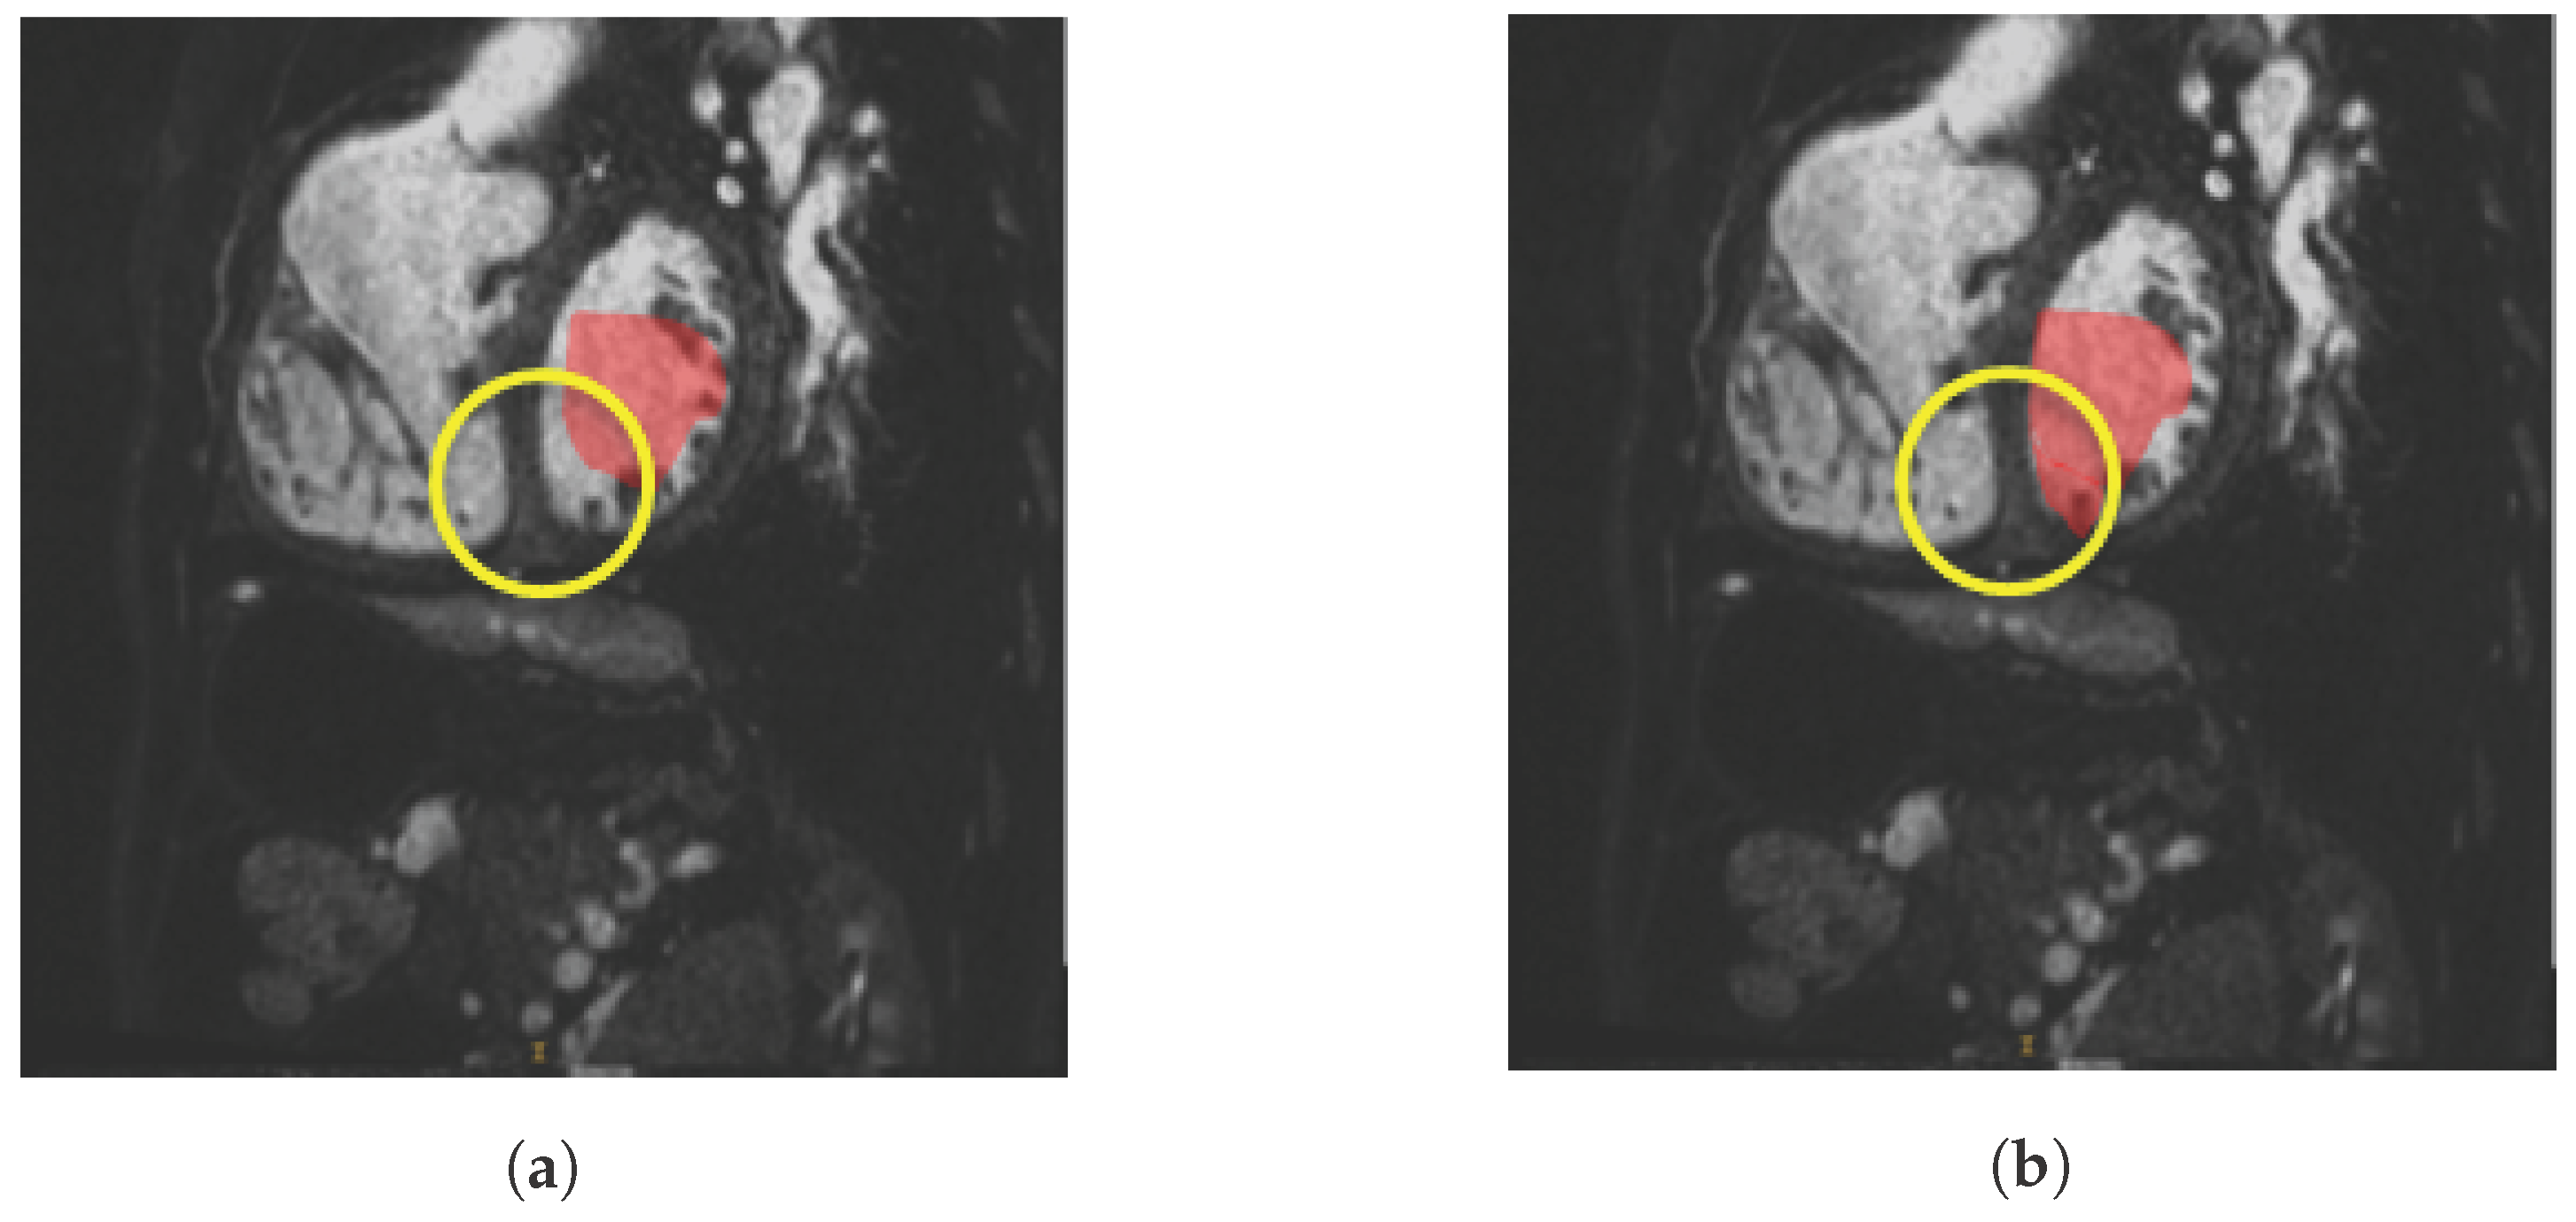

2.1. Smart Brush

3.1. Smart Brush Evaluation